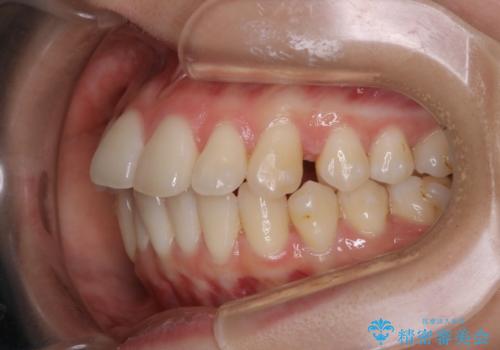

非抜歯でも劇的変化 インビザライン矯正治療

- 前歯のガタつきと噛み合わせの改善を主訴に初診来院され、審査の結果マウスピース装置による非抜歯での矯正を行うこととなりました。

元々の顎骨や口腔・歯槽骨が小さく、どうしても歯が並びきらない状況になっていました。マイクロインプラントという固定源からゴムかけを行うなど、補助装置を活用しながら臼歯部を順番に遠心方向(奥)に移動させていくことで抜歯をしなくても歯が並ぶよう計画を立てました。

歯のガタつきを治すため矯正治療を希望。審査の結果、非抜歯での矯正が可能であるという見通しが立ったためインビザラインによる非抜歯矯正治療を行った。

歯を並べるスペースを作るために、歯の遠心移動と歯列の拡大、歯自体を少しだけ小さく削る(IPR)という方法を複合的に組み合わせて配列を行いました。遠心移動用のゴムかけにはマイクロインプラントという小さいネジを用いて骨に直接固定源を求めました。